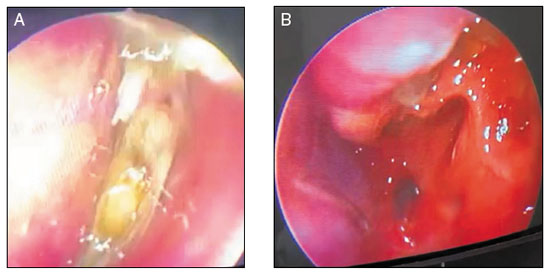

Figura 1

Endoscopia nasal pré-dupilumabe (A) e após 8 semanas de tratamento (B)

No caso relatado, a paciente apresentava todos os critérios clínico-laboratoriais estabelecidos para o diagnóstico de RSCcPN com inflamação tipo 2 (Tabela 1, Figura 1)16. Evoluiu com piora clínica progressiva, caracterizada pela recorrência dos pólipos, refratários aos tratamentos clínico e cirúrgico, coexistência de asma não controlada, resultando em perda significativa da sua qualidade de vida. Considerando a gravidade do quadro clínico, especialmente pela recorrência dos pólipos e uso frequente de corticosteroides sistêmicos, optou-se por iniciar o dupilumabe, 300 mg SC a cada duas semanas, na tentativa de controlar o processo inflamatório nasal. Após oito semanas, evoluiu com melhora clínica significativa, corroborada pelos escores SNOT-22, EVA e NPS, mantendo a asma controlada pelo ACT (Tabela 2). A paciente não apresentou nenhum evento adverso durante o período.